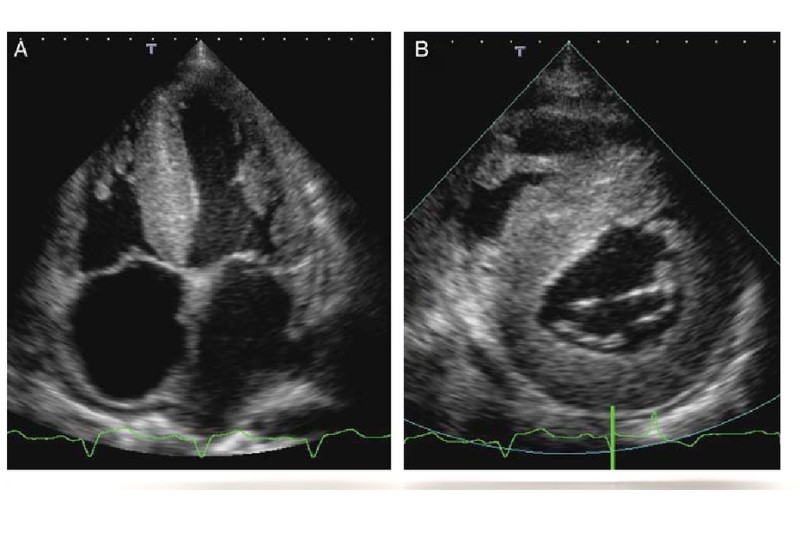

Siêu âm tim: Siêu âm tim bệnh cơ tim hạn chế giúp bác sĩ quan sát kích thước buồng tim, độ dày thành tim và đặc biệt là đánh giá chức năng tâm trương – dấu hiệu điển hình của bệnh khi tâm thất không thể giãn ra đủ để nhận máu.

Siêu âm tim cho thấy thất có kích thước bình thường hoặc nhỏ, thành thất dày giả, nhĩ giãn rõ. – Ảnh: Internet